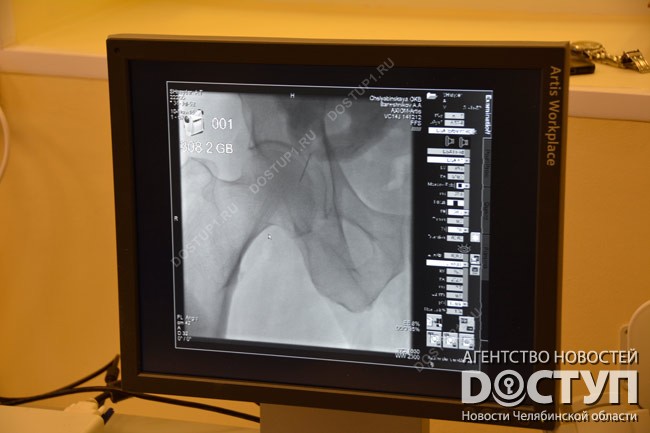

Суть данных операций в следующем: путем пункции сосудов в место сужения вводится специальный инструмент – оно расширяется и здесь устанавливается специальная металлическая арматура – стент, который призван предупредить формирование тромба, а следовательно, гангрены и некроза.